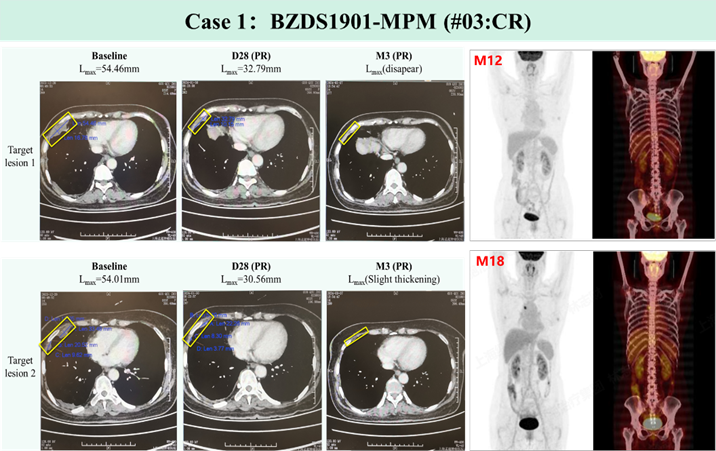

(2) 全球首个自分泌PD1纳米抗体靶向间皮素CAR-T疗法(BZDS1901):自主创新,实体瘤治疗迈向国际化

晚期恶性间皮瘤患者治疗难度大,标准治疗失败后中位生存期仅1年,5年生存率不足10%。作为全球首个自分泌PD1纳米抗体靶向间皮素CAR-T疗法,基于自主JL-闪-CAR-T工艺制备的BZDS1901展现出显著临床疗效。累计入组的12例标准治疗失败患者中,疾病控制率高达91.7%,客观缓解率41.7%,完全缓解率16.7%,其中1例患者持续完全缓解已达24个月。全球首个自分泌PD1纳米抗体靶向间皮素CAR-T疗法治愈的第1例恶性间皮瘤患者已持续完全缓解达62个月,为MSLN阳性实体肿瘤患者带来治愈性治疗希望。

凭借其独特的临床价值,集团与澳大利亚Adalta公司达成战略合作,推进全球临床验证与上市,标志着集团实体瘤细胞治疗迈入国际化发展阶段。由上海细胞治疗集团联合上海大学附属孟超肿瘤医院、中国科学院分子细胞科学卓越创新中心、中国医学科学院肿瘤医院、同济大学附属上海市第十人民医院及郑州大学第一附属医院等单位完成国际首个纳米抗体装甲化CAR-T细胞(NAC-T)的临床研究,发表于《Advanced Science》(IF=14.1),相关临床数据亦入选2025年5月第61届美国临床肿瘤学会(ASCO)年会。